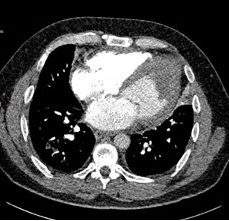

A 49-year-old male with no prior comorbidities presented to the emergency room (ER) with a 7-day history of fever, cough and shortness of breath. On admission, the patient had a blood pressure of 80/56 mmHg, a heart rate of 120 bpm, a respiratory rate of 36/minute, elevated jugular venous pressure, clear lung fields and muffled heart sounds on auscultation. An electrocardiogram was done, which showed sinus tachycardia with low-voltage QRS complexes. A screening bedside echocardiogram showed a large pericardial effusion (maximum thickness of 28 mm) with right ventricular diastolic collapse, suggestive of tamponade physiology. A bedside echocardiography-guided pericardiocentesis was attempted in the ER. Initially, 15 ml of haemorrhagic fluid was drained, after which no further fluid was drained. Cardiology consultation was obtained, and the patient was transferred to the cardiac catheterization laboratory.